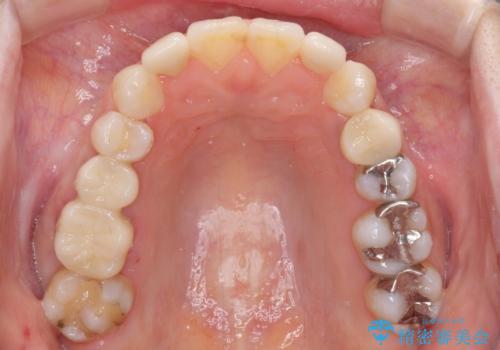

複数歯の補綴治療を行う場合、仮歯やセラミッククラウンを装着する度に保定装置を作り替える必要があり、その度に後戻りを起こす可能性が高くなります。

インビザラインであれば、矯正治療後半で補綴治療を行い、その後矯正治療を継続することでスムーズに治療を終えることができます。